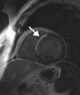

Myocardial infarction

A myocardial infarction (MI), commonly known as a heart attack, occurs when blood flow decreases or stops to a part of the heart, causing damage to the heart muscle. The most common symptom is chest pain or discomfort which may travel into the shoulder, arm, back, neck or jaw. [Source: Wikipedia ]